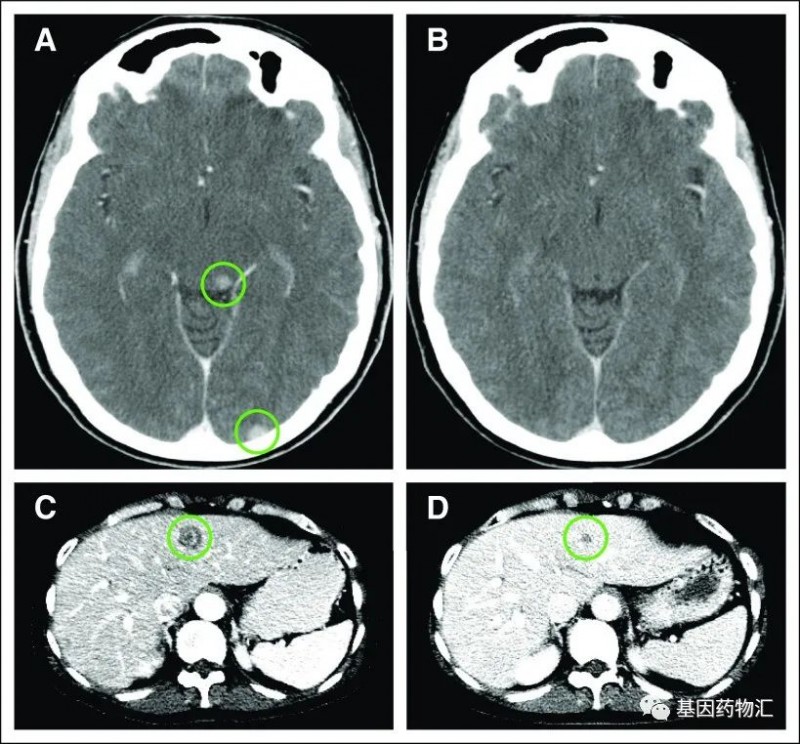

乳腺癌NTRK基因融合突变,NTRK抑制剂治疗后全身病灶缩小过半、脑转移病灶全部消失 乳腺癌

乳腺癌乳腺癌NTRK基因融合突变,NTRK抑制剂治疗后全身病灶缩小过半、脑转移病灶全部消失

乳腺癌NTRK基因融合突变,NTRK抑制剂治疗后全身病灶缩小过半、脑转移病灶全部消失“广谱抗癌药”指一类能够广泛应用于某种特定突变类型的各类实体瘤治疗的药物。只要符合分子分型的要求,广谱抗癌药可以忽略患者的病理分型或癌种,普遍地发挥出比较出色的治疗效果。NTRK就是这样一个靶点。在许多常见(例如肺癌、乳腺癌等)或不常见(如唾液腺癌、肉瘤等)的癌症患者当中,都